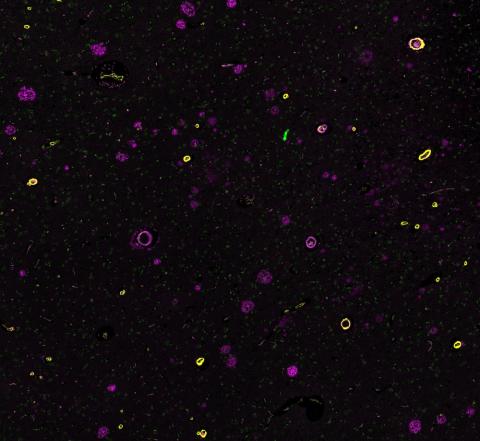

In the Alzheimer’s brain, there is a build-up of abnormal proteins in and around the cells, known as amyloid beta and tau. These stick together to form structures known as amyloid beta plaques and tau neurofibrillary tangles. These structures are linked to poor functioning, and the eventual loss, of neurons, which leads to the gradually worsening symptoms of the condition.

The main pathological protein hallmarks of Alzheimer's - amyloid beta plaques and tau neurofibrillary tangles. Credit: NIH.